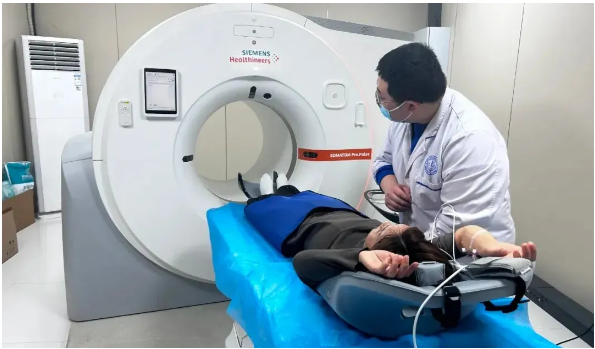

有高血压、高血脂、糖尿病等基础疾病,日常常出现胸闷、胸痛、心慌等症状,或有冠心病家族史的人群,可选择西门子双源CT进行冠脉CTA检查。这款设备扫描速度极快,一次屏气约5 - 6秒就能完成心脏冠脉检查,即便老年体弱、无法长时间憋气的患者也能轻松耐受。它能清晰显示冠脉血管的狭窄程度、斑块情况,精准排查冠心病等心血管疾病风险,实现早发现、早干预。

长期吸烟、经常接触粉尘或化学物质,以及有咳嗽、咳痰、咯血、胸痛等呼吸道症状的人群,双源CT是理想选择。它辐射剂量仅为普通CT的1/3,安全可靠,同时具备超高的空间分辨率,能精准筛查肺结节、肺癌、肺炎等肺部疾病,甚至可以发现直径极小的早期病变,为肺部健康筑牢防线。

若存在气道狭窄、气道异物等气道相关问题,双源CT的大范围扫描能力可清晰展示气道全貌,帮助医生准确判断病情,制定合适的治疗方案。

遭遇外伤后,怀疑有骨折、脱位情况,尤其是肋骨、脊柱等隐蔽部位骨折,双源CT能快速清晰地呈现骨折部位、移位程度等细节,为后续的复位、固定治疗提供精准指导。